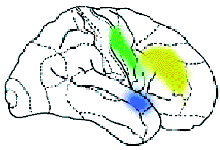

Найдены микроучастки мозга, которые отвечают за счёт, за различение конкретных и абстрактных слов. Показаны различия в работе нейронов при восприятии слова родного языка (чашка), квазислова родного языка (чохна) и слова иностранного (вахт — время по-азербайджански). В этой деятельности по-разному участвуют нейроны коры и глубоких структур мозга. В глубоких структурах в основном наблюдается увеличение частоты электрических разрядов, не очень „привязанное“ к какой-то определённой зоне. Эти нейроны как бы любую задачу решают всем миром. Совершенно другая картина в коре головного мозга. Один нейрон словно говорит: „А ну-ка, ребята, помолчите, это моё дело, и я буду выполнять его сам“. И действительно, у всех нейронов, кроме некоторых, понижается частота импульсации, а у „избранников“ повышается. Благодаря технике позитронно-эмиссионной томографии (или сокращённо ПЭТ) стало возможно детальное изучение одновременно всех областей мозга, отвечающих за сложные „человеческие“ функции. Суть метода состоит в том, что малое количество изотопа вводят в вещество, участвующее в химических превращениях внутри клеток мозга, а затем наблюдают, как меняется распределение этого вещества в интересующей нас области мозга. Если к этой области усиливается приток глюкозы с радиоактивной меткой — значит, увеличился обмен веществ, что говорит об усиленной работе нервных клеток на этом участке мозга. А теперь представьте, что человек выполняет какое-то сложное задание, требующее от него знания правил орфографии или логического мышления. При этом у него наиболее активно работают нервные клетки в области мозга, „ответственной“ именно за эти навыки. Усиление работы нервных клеток можно зарегистрировать с помощью ПЭТ по увеличению кровотока в активизированной зоне. Таким образом удалось определить, какие области мозга „отвечают“ за синтаксис, орфографию, смысл речи и за решение других задач. Например, известны зоны, которые активизируются при предъявлении слов, неважно, надо их читать или нет. Есть и зоны, которые активизируются, чтобы „ничего не делать“, когда, например, человек слушает рассказ, но не слышит его, следя за чем-то другим. Что такое внимание? Не менее важно понять, как „работает“ внимание у человека. Этой проблемой в нашем институте занимается и моя лаборатория, и лаборатория Ю.Д. Кропотова. Исследования ведутся совместно с коллективом учёных под руководством финского профессора Р. Наатанена, который открыл так называемый механизм непроизвольного внимания. Чтобы понять, о чём идёт речь, представьте ситуацию: охотник крадётся по лесу, выслеживая добычу. Но он и сам является добычей для хищного зверя, которого не замечает, потому что настроен только на поиск оленя или зайца. И вдруг случайный треск в кустах, может быть, и не очень заметный на фоне птичьего щебета и шума ручья, мгновенно переключает его внимание, подаёт сигнал: „Рядом опасность“. Механизм непроизвольного внимания сформировался у человека в глубокой древности, как охранный механизм, но работает и сейчас: например, водитель ведёт машину, слушает радио, слышит крики детей, играющих на улице, воспринимает все звуки окружающего мира, внимание его рассеянно, и вдруг тихий стук мотора мгновенно переключает его внимание на машину — он осознаёт, что с двигателем что-то не в порядке (кстати, это явление похоже на детектор ошибок). Такой переключатель внимания работает у каждого человека. Мы обнаружили зоны, которые активизируются на ПЭТ при работе этого механизма, а Ю.Д. Кропотов исследовал его с помощью метода имплантированных электродов. Иногда в самой сложной научной работе бывают смешные эпизоды. Так было, когда мы в спешке закончили эту работу перед очень важным и престижным симпозиумом. Ю.Д. Кропотов и я поехали на симпозиум делать доклады, и только там с удивлением и „чувством глубокого удовлетворения“ неожиданно выяснили, что активизация нейронов происходит в одних и тех же зонах. Да, иногда двоим сидящим рядом надо поехать в другую страну, чтобы поговорить.